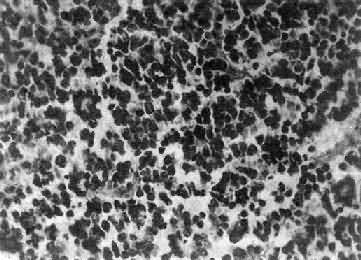

镜下,瘤细胞大小均匀,形态单一,弥漫排列,胞核居中着色深,胞浆空,环绕胞核形成空晕。间质富有血管,有不同程度的内皮细胞增生。约有20%病例可出现瘤细胞钙化,其范围大小不一,其中7%为镜下钙化,有时钙化灶较大,可在X线片上显示出来。如肿瘤组织中混有星形胶质细胞瘤成分达到50%,则称混合性少突星形胶质细胞瘤。

图16-25 室管膜瘤

瘤细胞为圆形或卵圆形,核染色质丰富,胞浆少,可见有细长的胞浆突起与血管相连,呈放射关,形成假菊形团